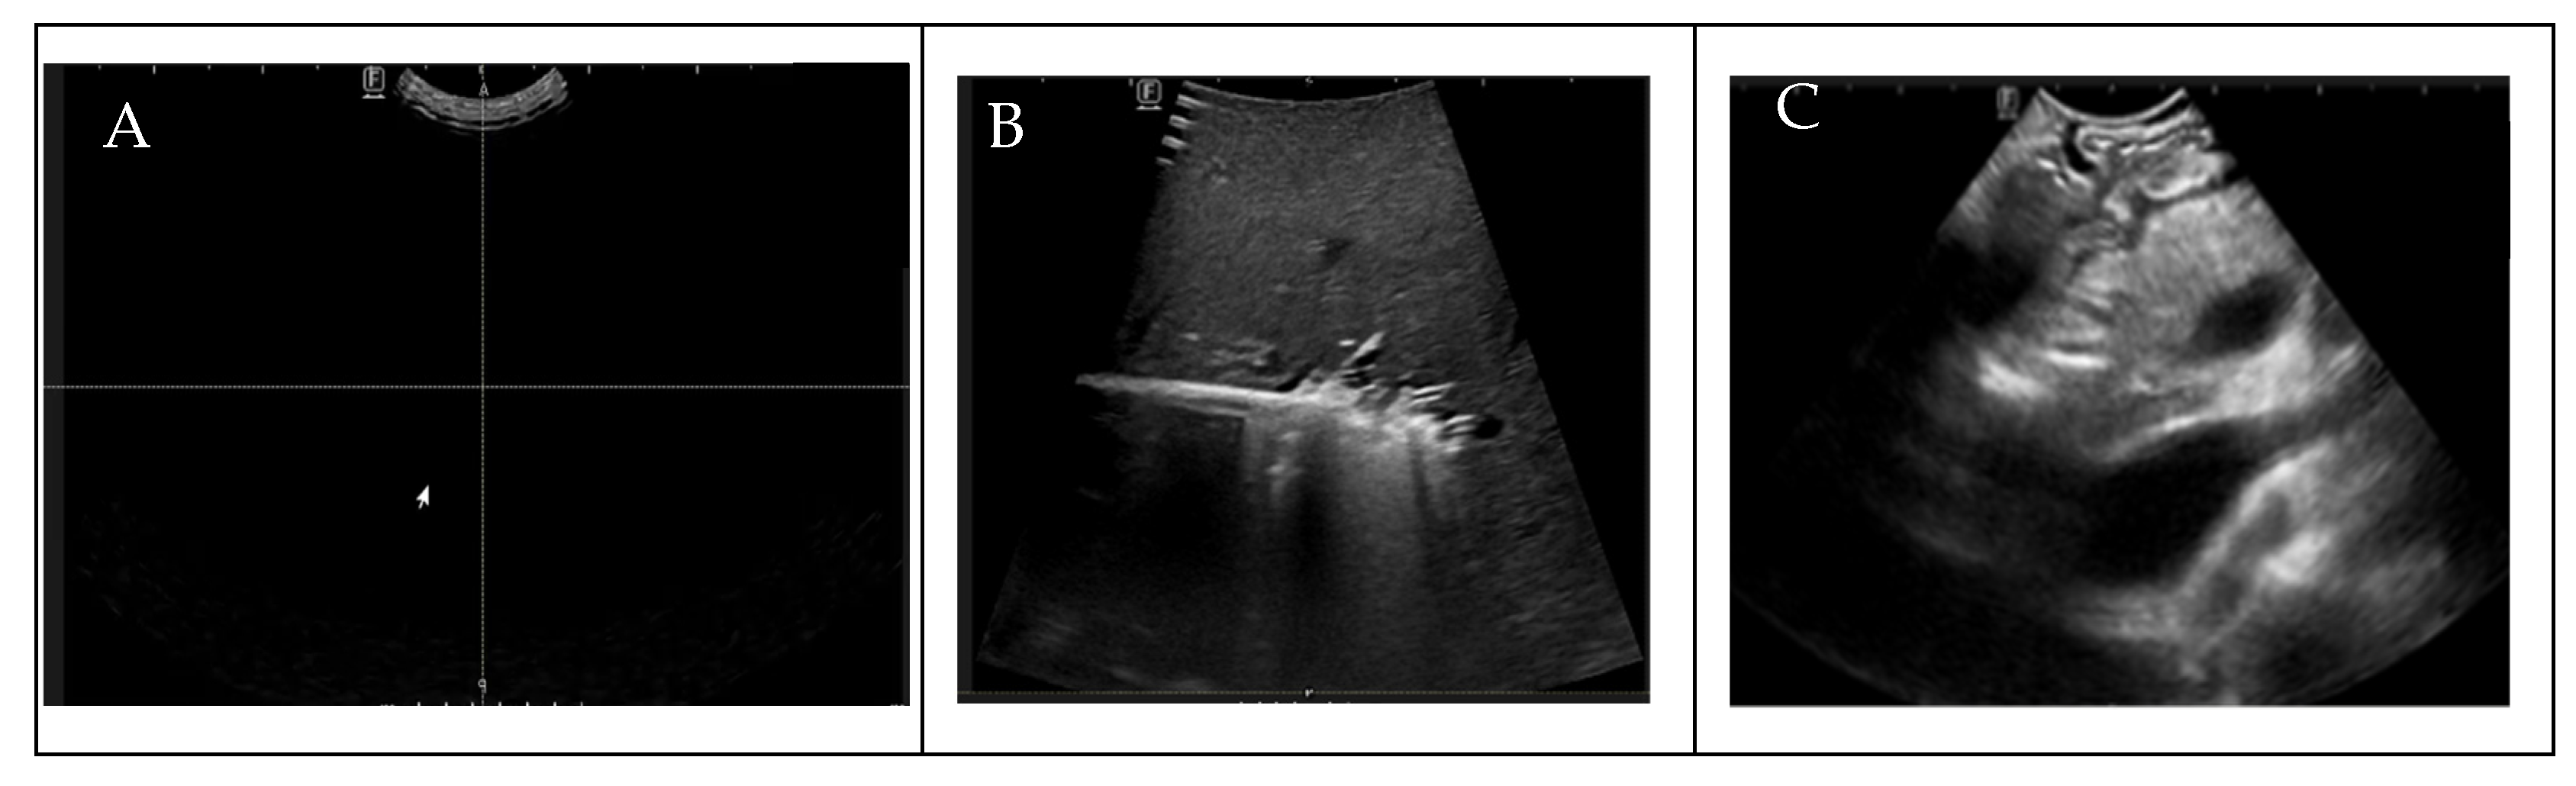

2.1. Data Preparation

2.3. Pre-Processing